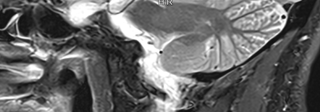

If you’ve ever seen an MRI scan of the brain, you might have noticed intricate, branching white lines deep inside the cerebellum. This mesmerizing structure has a poetic name: the arbor vitae, Latin for “tree of life.” I stumbled upon this term while reviewing my own MRI results, sparking a fascination with this lesser-known marvel of human anatomy.

The arbor vitae is the white matter of the cerebellum, the brain region responsible for coordination, balance, and fine motor skills. Its name comes from its striking appearance—branching, tree-like patterns formed by bundled nerve fibers that transmit signals across the cerebellum.

- Appearance: White, leaf-like streaks visible in sagittal MRI scans.

Modern brain imaging makes this “tree” visible like never before. On T1- or T2-weighted MRI scans (especially sagittal views), the arbor vitae appears as bright white streaks against the cerebellum’s gray matter.